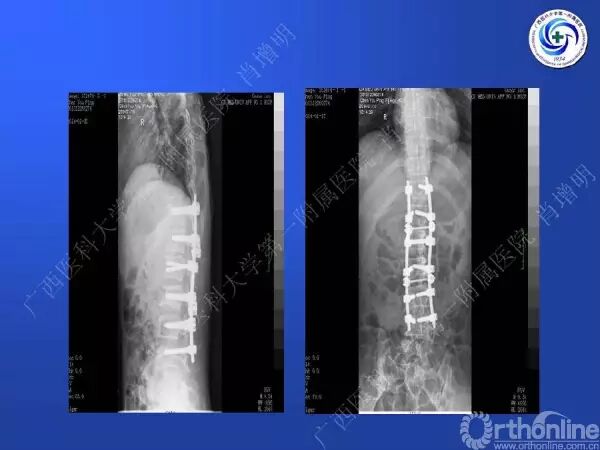

退变性脊柱侧凸多发于50岁以上的中老年群体,是现代常见的老年疾病。多年来,针对该病的临床研究一直没有停步,广西医科大学第一附属医院肖增明教授细致地介绍了该病的诊疗进展。